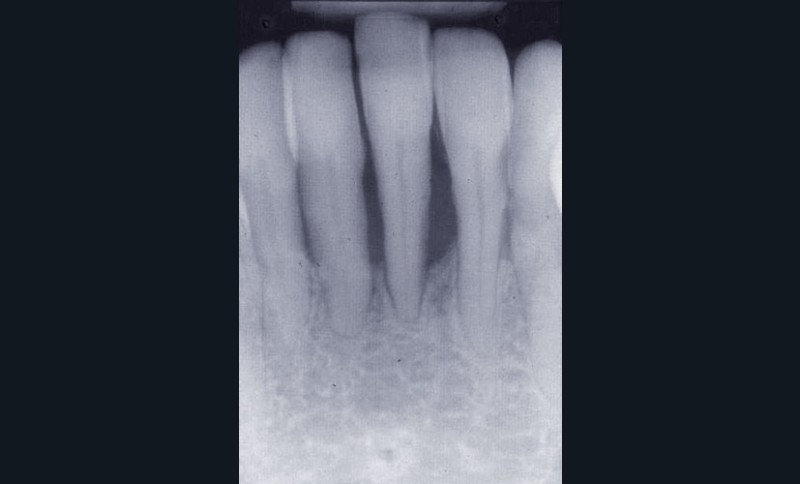

Les examens cliniques et radiographiques montrent une parodontite chronique généralisée (fig. 1a à m).

Nous décidons d’entreprendre une thérapeutique initiale parodontale classique dans tous les secteurs, y compris l’extraction de 24, un bridge de 45 à 48 avec 46 en pontique, un bridge complet de contention de 17 à 27 sur 11 piliers dentaires et une greffe épithélio-conjonctive sur 31. Cette dernière ne sera jamais réalisée. Le bridge maxillaire permettra de réduire le surplomb antérieur et d’améliorer le sourire de la patiente, ce qui constitue l’une de ses demandes.